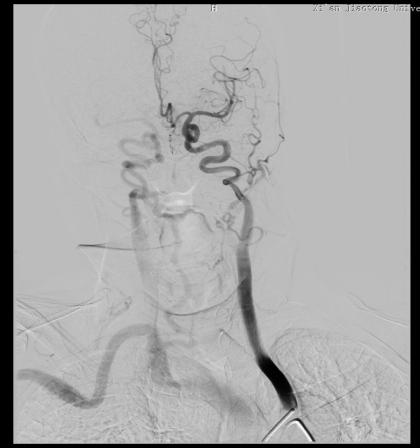

患者武某,女,75岁,因言语含糊伴右侧肢体无力3小时入院。行头颅CT未见明显出血病灶,颅脑DWI示:左侧额叶及枕叶可见新发病灶。遂以“急性脑血管病”收住神经内科。结合患者病史系统完善检查,既往有“心房纤颤”病史,未使用药物治疗,有“高血压”病史5年余,测最高血压180mmHg,现口服坎地沙坦降压,自诉血压控制尚可。有脑心血管造影检查手术指征,无手术禁忌症,建议患者进行全脑血管造影及冠脉造影术。而完成两个部位造影就意味着要行两次手术,两次手术不仅增加患者的痛苦,还给患者增加了经济负担。急患者之所急,想患者之所想,经过神经内科张茹副主任、范清雨医生和心血管内科蒋伟副主任医生详细讨论并做好全面评估后,共同为患者制定了冠脉造影检查后行全脑血管造影检查的手术方案,既可以明确病情,又可以减少患者痛苦。

告知患者及家属全脑血管造影及冠脉造影相关手术风险后,家属表示理解并签字同意全脑血管造影及冠脉造影术。手术如期进行,在神经内科导管室为患者实施了“经股动脉行全脑血管造影术+冠状动脉造影术”。手术历时1小时05分,科室之间配合默契,顺利完成此次手术。

此项技术是在脑血管造影基础上同时进行心血管造影,一次穿刺就可以检查“脑”血管和“心”血管,将原本需要两次才能完成的检查一次性完成,不仅减少了患者反复动脉穿刺的痛苦,也极大地缩短了检查时间,降低了检查及治疗费用。此次多学科联合诊疗,制定脑心血管同时造影,为患者寻找出了病因,共同为患者的生命健康保驾护航!